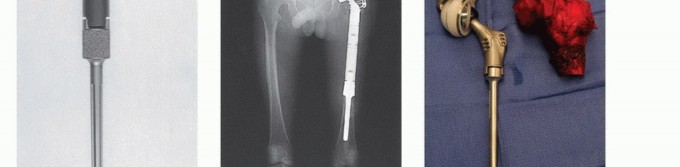

استبدال عظم الفخذ البعيد

يُعد عظم الفخذ البعيد هو الموقع الأكثر شيوعًا للأورام العظمية الأولية. تتطلب إعادة بناء الطرف الصناعي الداخلي في هذه المنطقة (شكل 5) مزيجًا فريدًا من المرونة والاستقرار الكلي، حيث يتم إزالة محفظة الركبة والأربطة الصليبية والجانبية أثناء الاستئصال. يسمح مفصل الركبة المفصلي الدوار الحركي (Kinematic rotating hinge knee) والتصميمات المفصلية المماثلة المقيدة جزئيًا بمدى كبير من الثني والتمديد، بالإضافة إلى الدوران حول المحور التشريحي للركبة، مع توفير استقرار متأصل في المستويين الفاروس-فالجوس والأمامي الخلفي. نادرًا ما تكون إعادة بناء آلية الباسطة ضرورية، حيث يمكن غالبًا إنقاذ الرضفة أثناء الاستئصال. يمكن إعادة تسطيح الرضفة ولكنها غالبًا ما تكون غير ضرورية.

يُعتبر الأستاذ الدكتور محمد هطيف رائدًا في إجراءات استبدال عظم الفخذ البعيد في صنعاء، مستخدمًا أحدث الأنظمة المعيارية لضمان أفضل النتائج الوظيفية للمرضى.